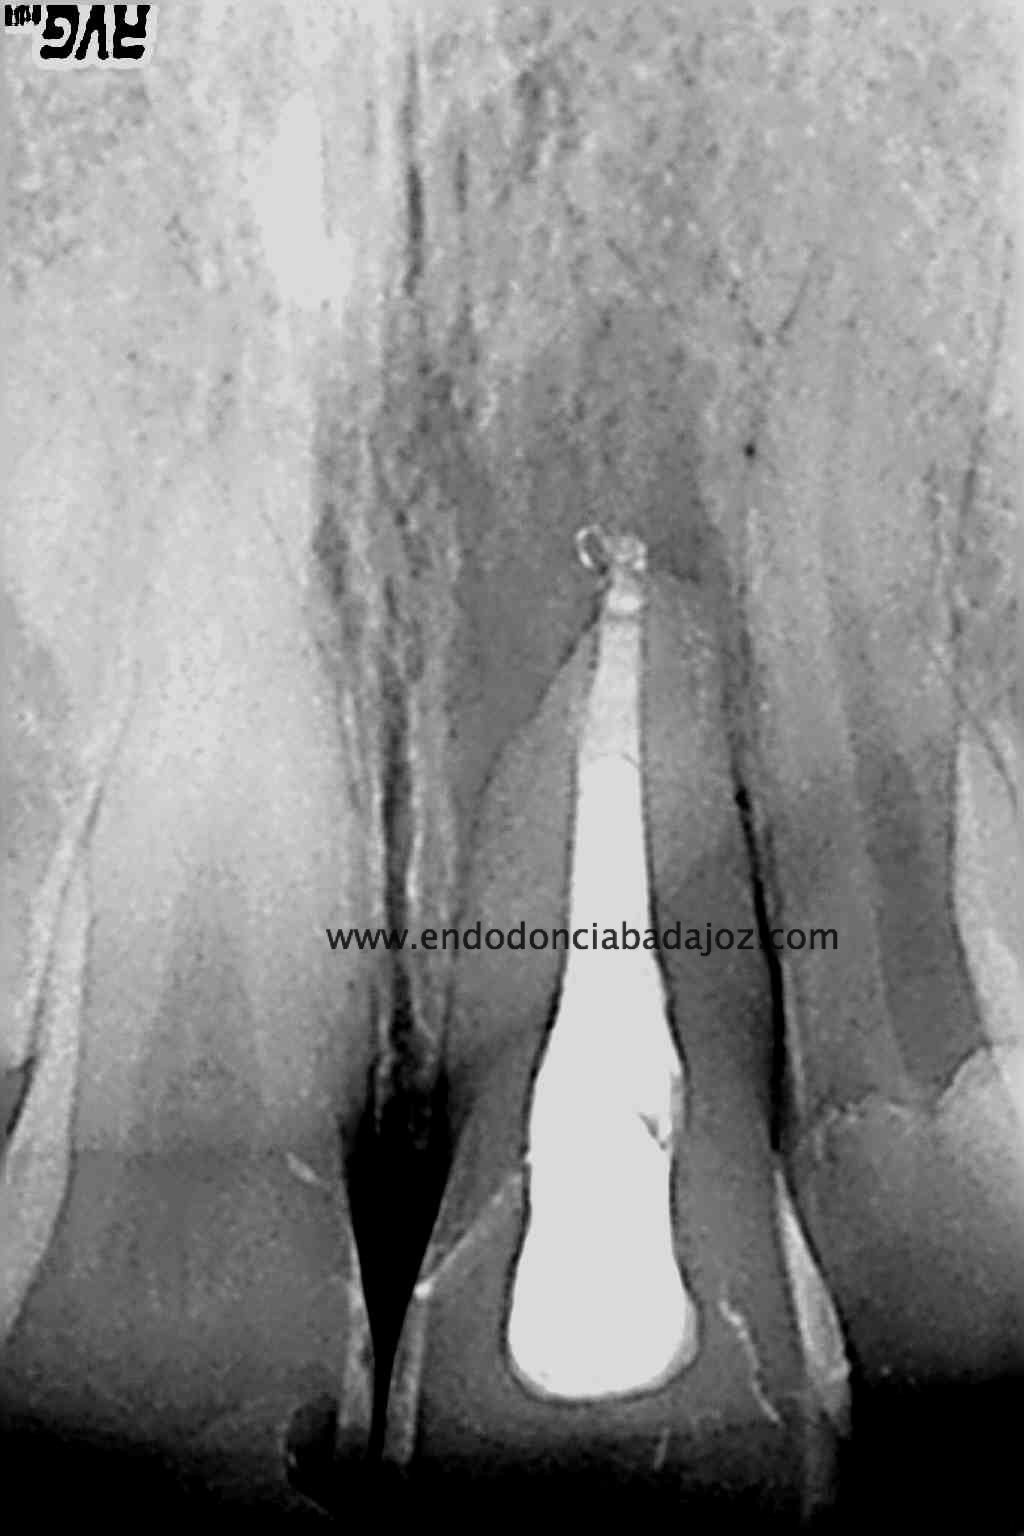

Colocamos la barrera apical verificando que conseguíamos un buen sellado:

(Rx Mesioradial)                                                               (Rx Ortoradial)

Una vez que hemos transportado y barrera apical, hacemos el backfilling con la Pistola Obtura II.